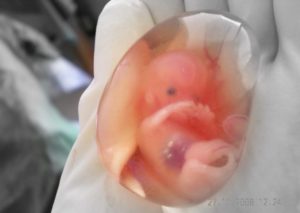

Невынашивание беременности — патология, при которой плод прекращает свое развитие и гибнет. Другое название этой патологии — замершая беременность. Ее разновидность – пустое плодное яйцо. В этом случае оплодотворение яйцеклетки происходит нормально, но дальше эмбрион не развивается.

Также о замирании беременности говорят в случае, если произошло зачатие и вслед за ним имплантация (то есть оплодотворенной яйцеклетке удалось прикрепиться), но развитие эмбриона по каким-то причинам не происходит. В этом случае формируются лишь внезародышевые органы, а ребенка в яйце – нет. Такое явление называется “пустым плодным яйцом”.